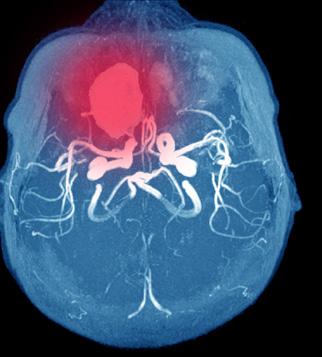

Standardiserte pasientforløp ved akutt hjerneblødning («Bundle of care»)

Ingen enkelttiltak har så langt, vist dokumentert effekt på funksjon etter hjerneblødning. Til gjengjeld viser nyere studier at man ved etablering av standardiserte pasientforløp, såkalte «bundle of care», reduserer dødeligheten og oppnår bedre funksjon etter 3 måneder (2, 3). Den kombinerte intervensjonen består av: 1) rask og vedvarende blodtrykkskontroll, spesifisert som systolisk blodtrykk <140 mmHg innen 1 time etter innkomst sykehus,

2) rask reversering av eventuell antikoagulerende legemidler, 3) vurdering av kirurgi, i tillegg til god homeostase gjennom kontroll av blodsukker (>6 til ≤ 10 mmol/L), behandling av feber med antipyretika, og forebygge og tidlig behandle komplikasjoner. (Figur 2)

Figur 2. Standardisert forløp ved akutt hjerneblødning består av 1) rask og vedvarende blodtrykkskontroll, 2) rask reversering av eventuell antikoagulerende legemidler, 3) vurdering av kirurgi, i tillegg av stabil homeostase gjennom kontroll av blodsukker, behandling av feber med antipyretika, og å forebygge og tidlig behandle komplikasjoner. Illustrasjon laget av forfatterne ved hjelp av Storyset.com og Shutterstock.